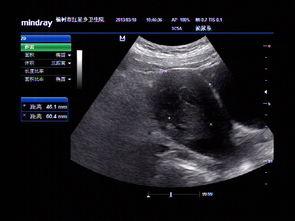

首先,得先弄清楚什么是子宫复位手法。简单来说,它是一种通过按摩和手法操作,帮助产后女性的子宫恢复到正常位置的方法。你知道吗,产后子宫的位置可能会因为分娩过程中的拉伸和压迫而发生变化,甚至出现子宫脱垂等问题。而子宫复位手法,就是用来解决这些问题的。

2. 促进子宫恢复:帮助子宫尽快回到原来的位置,减少子宫脱垂的风险。